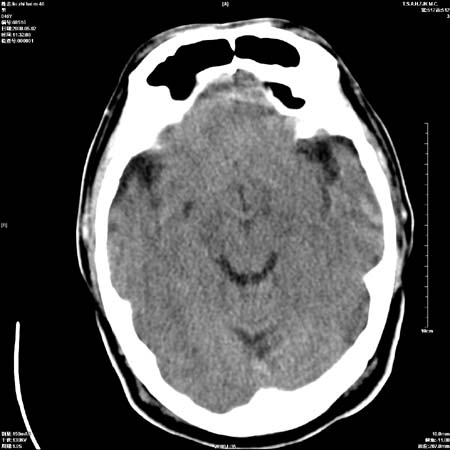

男性   46岁   头晕头痛一周    无任何外伤史    有高血压病史

亚急性硬膜下血肿

考虑双侧慢性硬膜下出血

支持双侧慢性硬膜下血肿。

应该是亚急性(3天——3周)硬膜下出血

亚急性硬膜下血肿;典型。